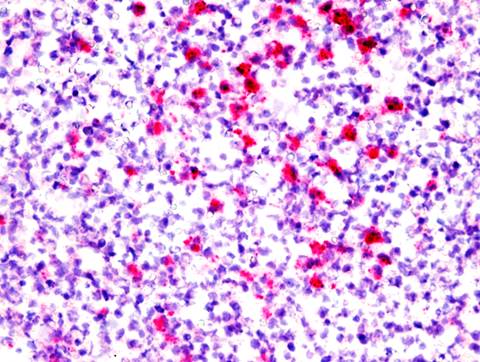

A la histopatología, las lesiones se caracterizaban por severa leptomeningitis, coroiditis, y periventriculitis fibrino-supurativa, con vasculitis leucocitoclástica, trombosis con numerosas colonias bacterianas cocoides Gram-negativas, y manguitos perivasculares de neutrófilos y macrófagos de 1-3 células de espesor.

Figura 3: Sistema Nervioso Central (Caso Nº 3). Región periventricular. Vasculitis, neutrófilos perivasculares, trombosis y numerosos biofilms de colonias bacterianas en la pared vascular (flecha). (H&E, x400).